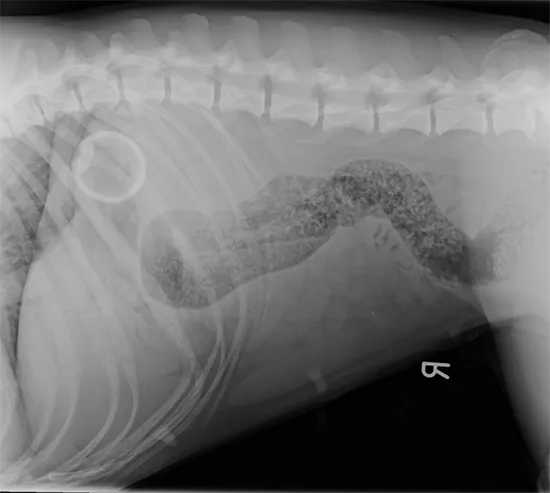

A romp in the park turned into a race to the vets after a young boxer dog swallowed a tennis ball which lodged dangerously in her stomach.